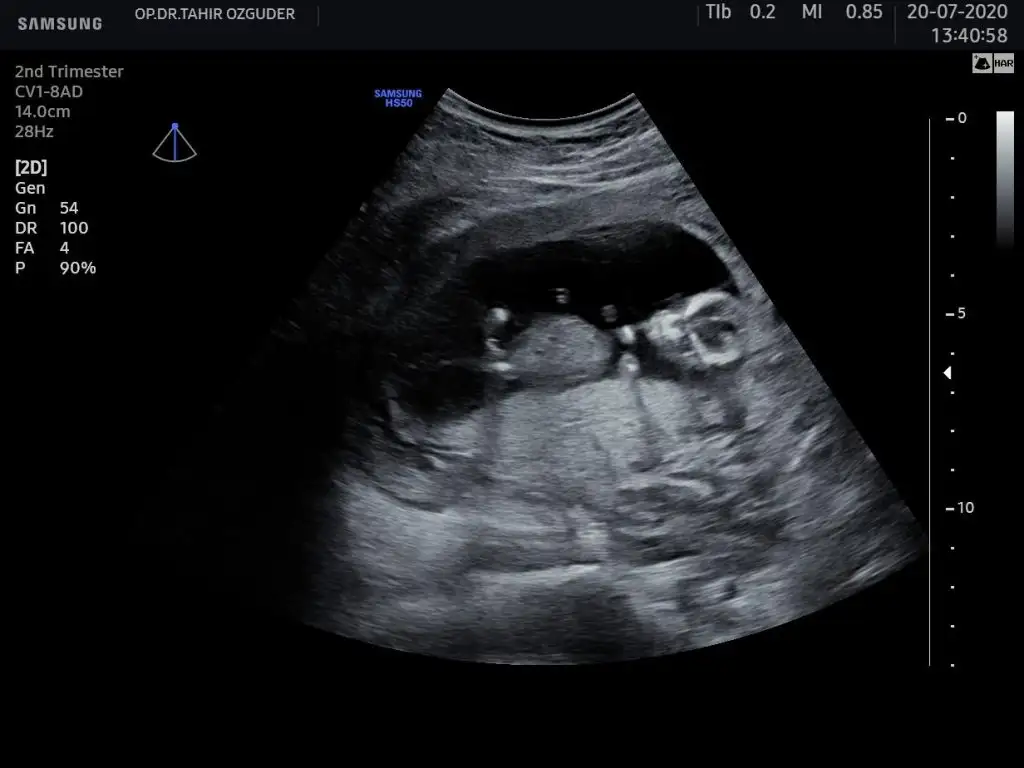

dr soylemeden siz gorun genital nub teorisi ( bebegin cinsiyeti)

Banada tahminde bulunabilir misinizzz🥰